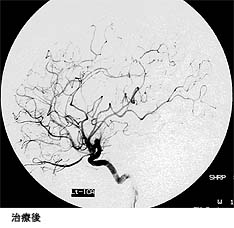

脳出血による半身麻痺と意識障害で発症した患者さんの治療前後の血管撮影を下に示します。(赤線内が脳動静脈奇形の部分)